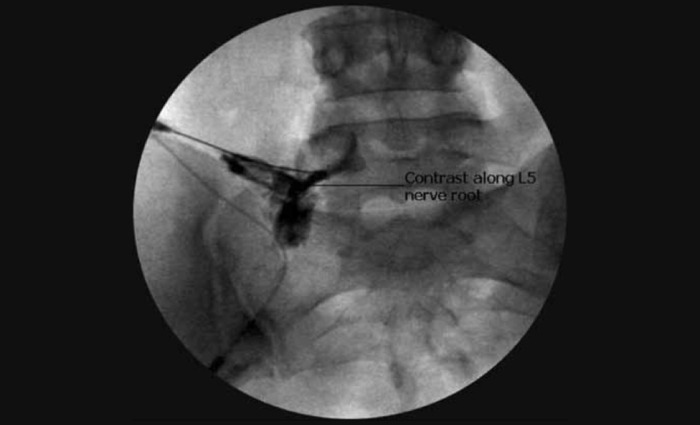

Imaging Studies:

MRI: Provides detailed images of soft tissues, including discs, nerves, and the spinal cord.

CT Scan: Offers detailed cross-sectional images of the spine.

X-Rays: Can help rule out other causes of back pain but do not show herniated discs directly.

Epidural Steroid Injections: To reduce inflammation and pain around the affected nerves.

Intradiscal Ozone : Injections to shrink the herniated disc and reduce pain.

Radiofrequency Ablation : Procedure to help block the painful nerves using heat energy resulting in long term pain relief.